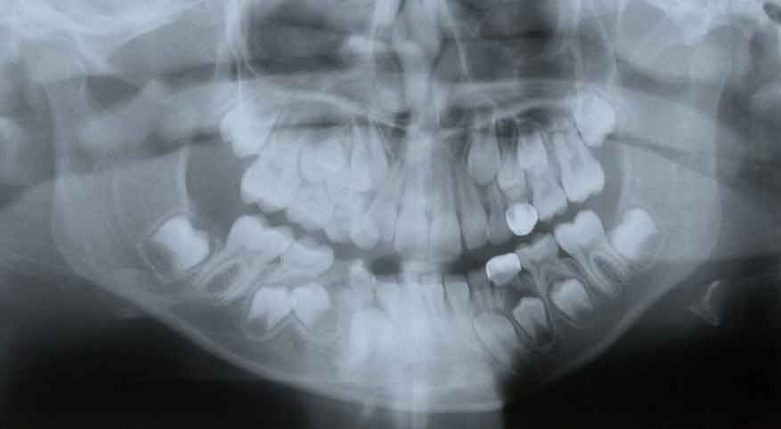

Odontograma

Odontograma QML plataforma Velneo. Acelere el desarrollo de aplicaciones para clínicas dentales con nuestro control Odontograma realizado en QML y JavaScript con Velneo V7.